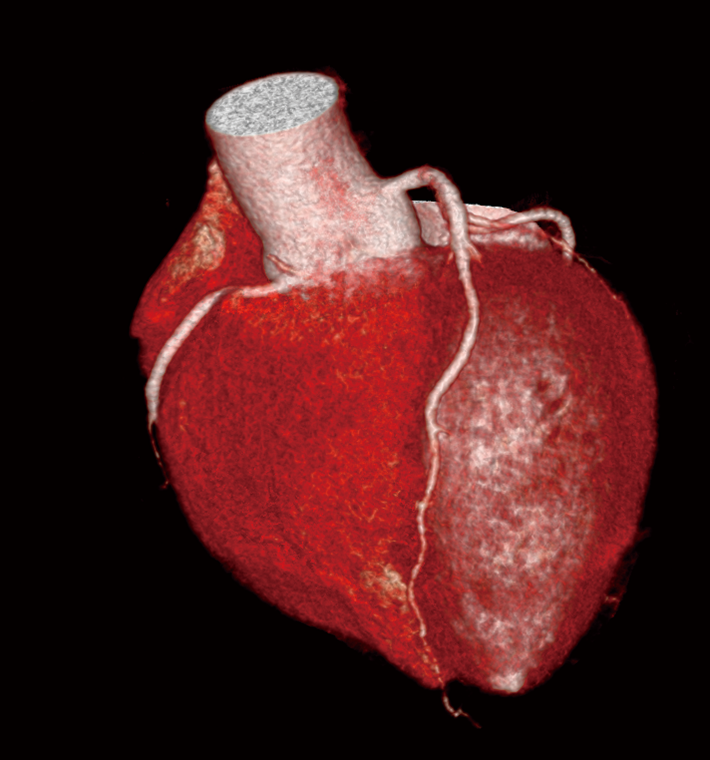

同一患者の冠動脈CT b 図3 冠動脈撮影 100kVによるFlash撮影